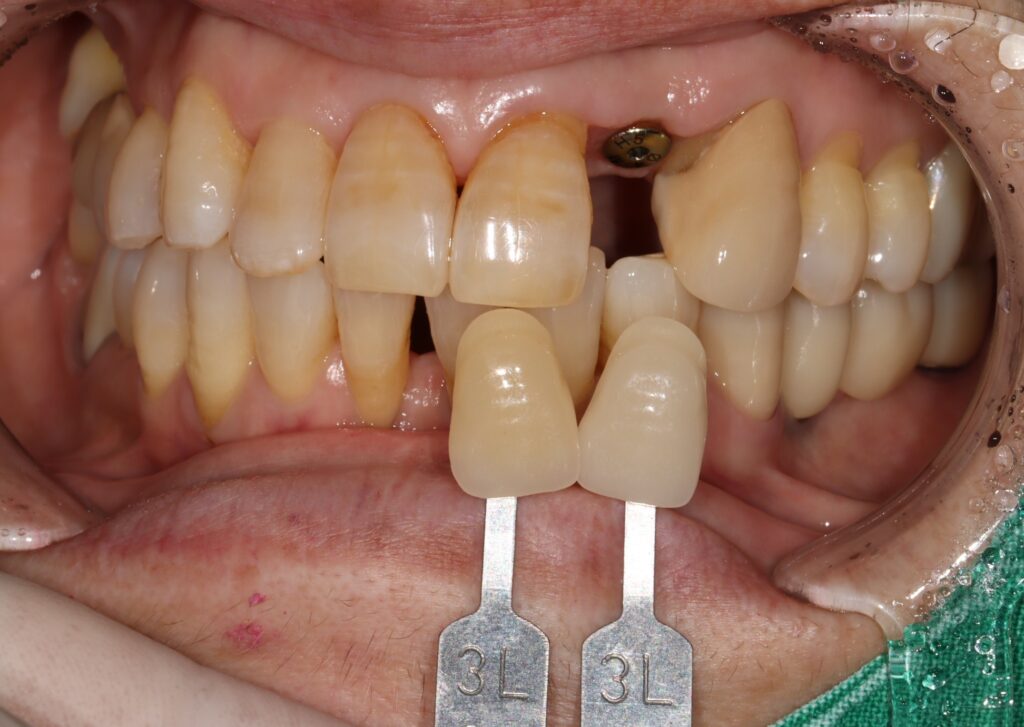

앞니의 색상을 결정하는 과정인데요.

앞니임플란트는 높은 난이도의 치료로

분류되는데 잇몸 라인과 치아의 색상·형태·배열까지

고려해야 하기 때문입니다.

자연치아와의 조화를 이루기 위해서는

의료진의 섬세한 판단과 풍부한 임상 경험이

필수적으로 을지로치과 선택 시에는

의료진의 경력과 앞니임플란트 시술 경험,

정품 재료 사용 여부, 합리적인 비용 체계 등을

종합적으로 확인하는 것이 바람직합니다.